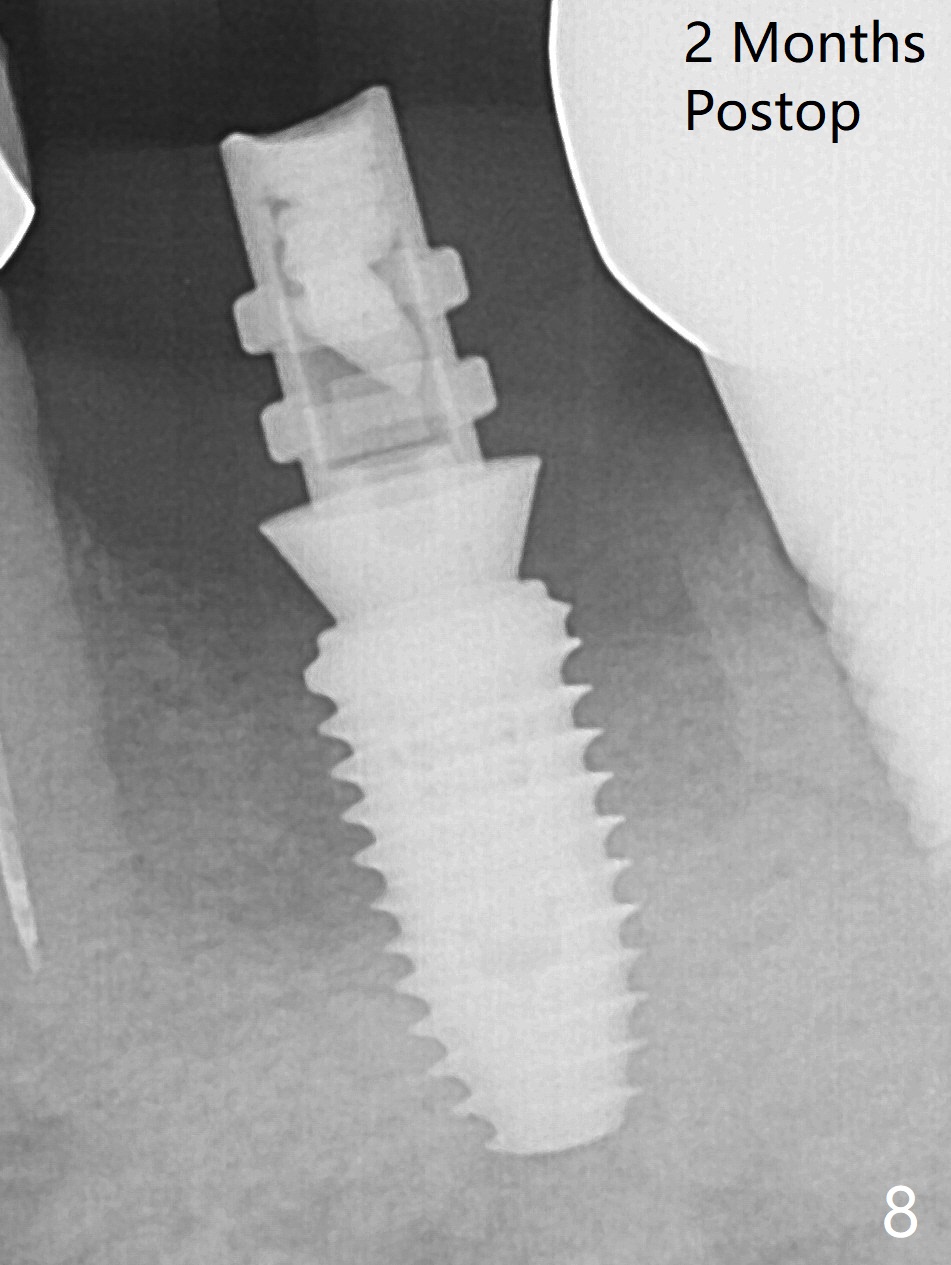

Extraction of the residual roots at #19 (Fig.1) is difficult, partially due to the hard one. The latter contributes to primary stability of 5x10 mm IS implant placed in the septum (Fig.2 (*),3). After change of cementation abutment (5.2x4.5(2) mm (short for provisional)) to hexed temporary abutment (5.2x8(2) mm), Collagen plug and Vera Graft are placed in the remaining mesial and distal socket (Fig.4 *). The last PA is taken when the temporary abutment (Fig.6 (<: hexed portion)) and provisional (P) are removed for modification. Before the abutment/provisional complex returns, a 2nd round of graft is placed (Fig.5 *). After the complex is seated, a 3rd round of graft is placed buccally (Fig.7). The temporary abutment is retightened 2 months postop (Fig.8). The implant appears to be osteointegrated 3.5 months postop (Fig.9). The gingiva looks healthy with (Fig.10) and without the provisional (Fig.11,12). It appears that there is no or minimal buccal plate loss. After insertion of a 5.7 x3 mm 15 degree (B-type) angled abutment (Fig.13) and height adjustment, impression is taken. The provisional is reseated after impression. The mesial bony defect seems to have been repaired nearly 8 months postop, 3 months post cementation (Fig.14 *). The bone density increases mesially 11 months post cementation (Fig.15).